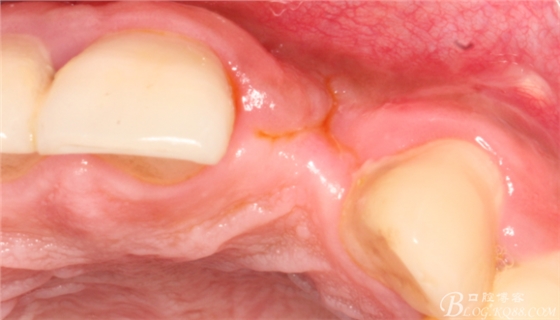

10天拆線一切正常,又過了兩周患者復(fù)診,自述期間無異常??趦?nèi)檢查,真的嚇了一跳,唇側(cè)鼓了個(gè)包,擠壓有白色分泌物溢出,絕對(duì)不是膿液,液體排除后,術(shù)區(qū)觸診空虛,外觀塌陷。這時(shí)候考研大夫的時(shí)刻到了,是先觀察一段時(shí)間再說?還是馬上進(jìn)行處理?我的回答是:馬上處理!如果你沒有及時(shí)處理,而是放患者回家觀察,那么接下來會(huì)發(fā)生如下情況:1.回家后患者家屬及親友會(huì)有很多你可以想象得到的討論;2.患者及家屬會(huì)對(duì)你產(chǎn)生不信任,勢(shì)必會(huì)到其他門診或醫(yī)院檢查,他院大夫會(huì)不會(huì)發(fā)表對(duì)你不利的言論;3甚至?xí)蚁嚓P(guān)法律界人士找你討要說法。